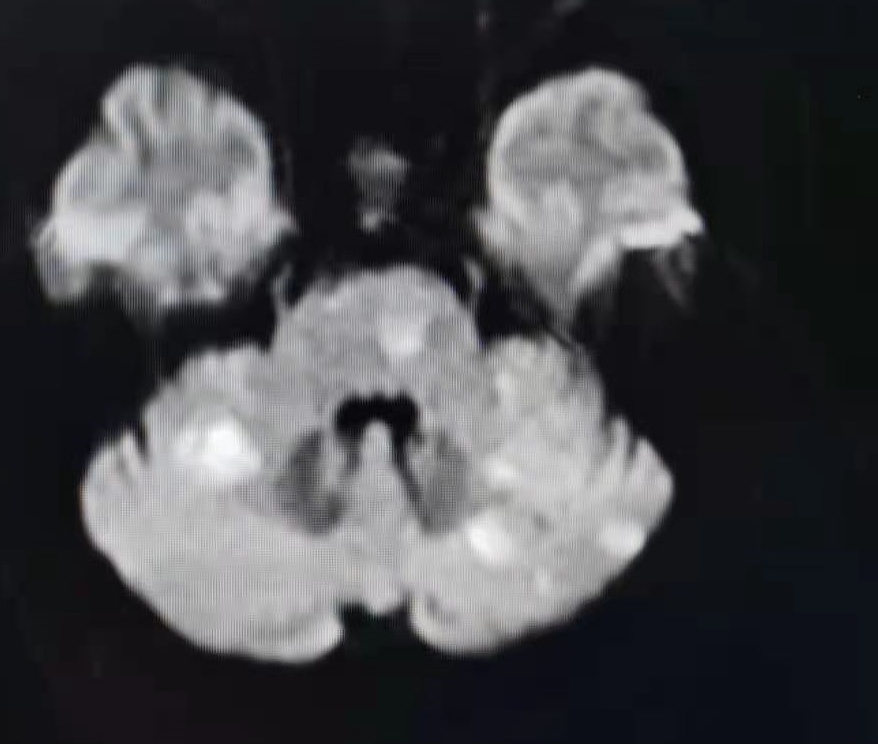

扩张后造影,提示恢复正向血流,残余狭窄50%左右。发现加奇SacSpeed® 2.5mm×9mm颅内球囊扩张部位存在双腔征,考虑血管夹层,给予替罗非班8ml/h持续泵入。